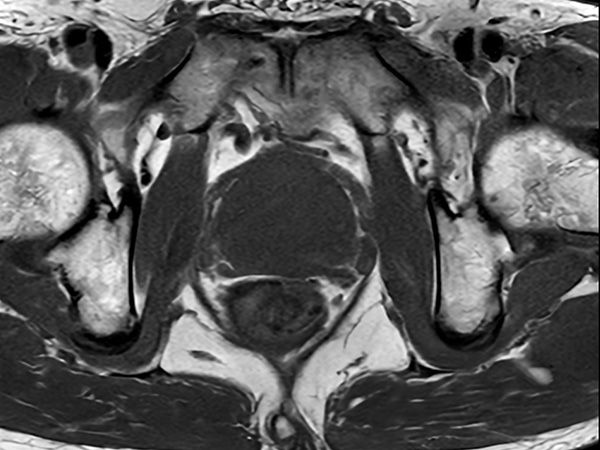

Fast Prostate imaging with SmartSpeed Precise

Kumamoto Chuo Hospital Japan